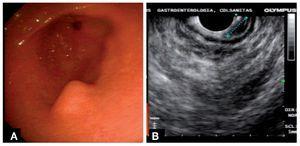

Hombre de 30 años de edad, sin antecedentes de importancia, referido para evaluación de lesión subepitelial, con sintomatología de dispepsia y distensión abdominal. A la exploración física con abdomen blando, depresible, no doloroso a la palpación sin otros hallazgos relevantes. Los estudios de sangre incluyendo amilasa y lipasa dentro de límites normales. La endoscopia de tubo digestivo alto mostró una lesión subepitelial sobre curvatura mayor del antro gástrico de aproximadamente 12 milímetros de diámetro con mucosa superficial normal. El estudio citopatológico informó mucosa gástrica normal. Se realizó una endosonografía con ecoendoscopio radial (Olympus GF-UE160), que mostró una lesión hipoecóica, homogénea, de bordes bien delimitados, que se origina en la muscularis de la mucosa de 12 milímetros sin evidencia de adenopatías (Figura 1). Se realizó resección endoscópica de la mucosa con un equipo de REM (Olympus K-009), que incluye un capuchón que se coloca en la punta del endoscopio; el capuchón tiene un borde interno en el que se coloca una asa electro-quirúrgica con forma de media luna. Posterior a la endosonografía se insertó un endoscopio terapéutico (Olympus GIF-H180) con el capuchón. Se inyectaron 5 mL de solución salina elevando la mucosa circundante, pero con mínima elevación de la lesión subepitelial y se aplicó una banda elástica en la base de la lesión. Se succionó la lesión dentro del capuchón con el asa colocada. El asa fue apretada y la lesión fue alejada del capuchón con visión directa para garantizar que no fuera capturada una cantidad excesiva de la pared gástrica. La lesión fue resecada utilizando corriente de corte y coagulación, extrayéndose con el endoscopio (Figura 2). No hubo complicaciones y el paciente fue egresado con la prescripción de un inhibidor de bomba de protones vía oral. La pieza de resección midió 11 milímetros. El examen histológico mostró mucosa gástrica antral normal suprayacente a estructuras ductales complejas en la muscularis de la mucosa y submucosa con proliferación de acinos pancreáticos e islotes de Langherhans con configuración lobular. El margen de profundidad estaba compuesto por submucosa sin tejido de la muscular propia (Figura 3).

¿ Figura 1. A. Endoscopia. Lesión subepitelial en curvatura mayor del antro gástrico. B. Endosonografía. Lesión hipoecoica de la segunda capa (muscularis de la mucosa) de la pared de antro gástrico.